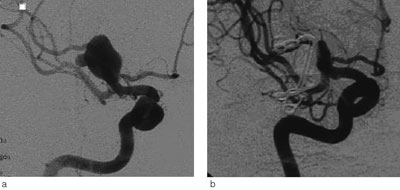

Universitetssykehuset er regionsykehus for vel 470 000 innbyggere i Helse Nord. Nevrokirurgisk avdeling har siden 1986 utført kirurgisk behandling av intrakraniale aneurismer (fig 1) (11). Endovaskulær behandling ble introdusert i 2000 (fig 2).

Vi behandlet 51 (63 %) av 81 rumperte aneurismer og 24 (75 %) av 32 ikke-rumperte aneurismer kirurgisk. Alle, unntatt to gigantaneurismer som ble pakket med gasbind og vevslim, ble lukket med klipsligatur. De øvrige 38 aneurismene (30 rumperte og åtte ikke-rumperte) ble behandlet endovaskulært med coiling. Blant pasienter som hadde hatt subaraknoidalblødning, var det ingen signifikant sammenheng mellom Hunt & Hess-grad eller Fisher-grad og valg av behandlingsmetode.

Behandlingsmetoden var avhengig av aneurismets lokalisasjon. Aneurismer utgående fra a. cerebri media ble vanligvis lukket med klipsligatur (43 av 46 tilfeller, 93 %), mens alle aneurismer i bakre kretsløp ble behandlet endovaskulært. For aneurismer utgående fra a. carotis interna og a. cerebri anterior var fordelingen av klipsligatur versus endovaskulær behandling henholdsvis 42 % versus 58 % og 58 % versus 42 %.